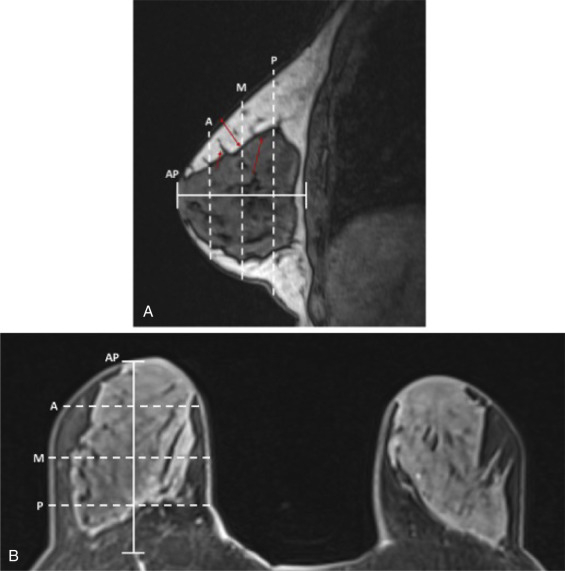

Next, NSM proceeds through the chosen mastectomy incision. Great care is taken to perform the mastectomy in the appropriate plane, being at the level of the superficial breast fascia (

). This is an anatomic plane that is present, but variably defined, in all individual patients using magnetic resonance imaging ( Fig. 22.2 ). It has been demonstrated that patients with thinner postoperative NSM flap thickness and a reduced post-/preoperative NSM flap thickness ratio have higher rates of reconstructive complications in NSM. This emphasizes the importance of precise dissection at this level to both maximize removal of breast tissue and perfusion of the breast envelope.

of AP distance; M, middle measurement at

AP distance; P, posterior measurement and

AP distance; short red arrow, Cooper’s ligament with breast tissue extending to dermis; long red arrow, anterior mammary fascia; double-headed red arrow, example of flap thickness measurement at middle location.